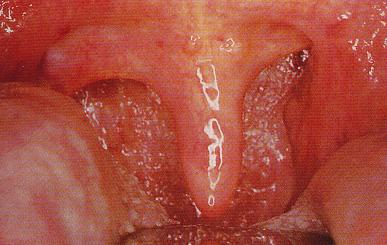

扁桃体脓肿

医生详解:扁桃体肿大的三种分度

临床上,根据扁桃体肿大的病情轻重,把扁桃体肿大分为三度:

I度:扁桃体肿大不超过咽腭弓

II度:超过咽腭弓

III度:肿大达咽后壁中线